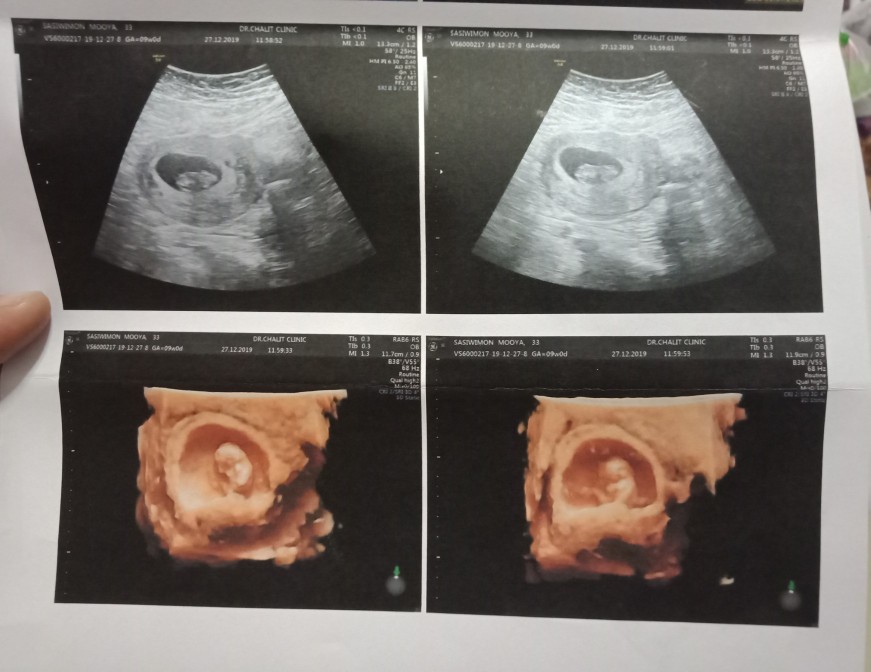

ตอน 10+3 w ค่ะ